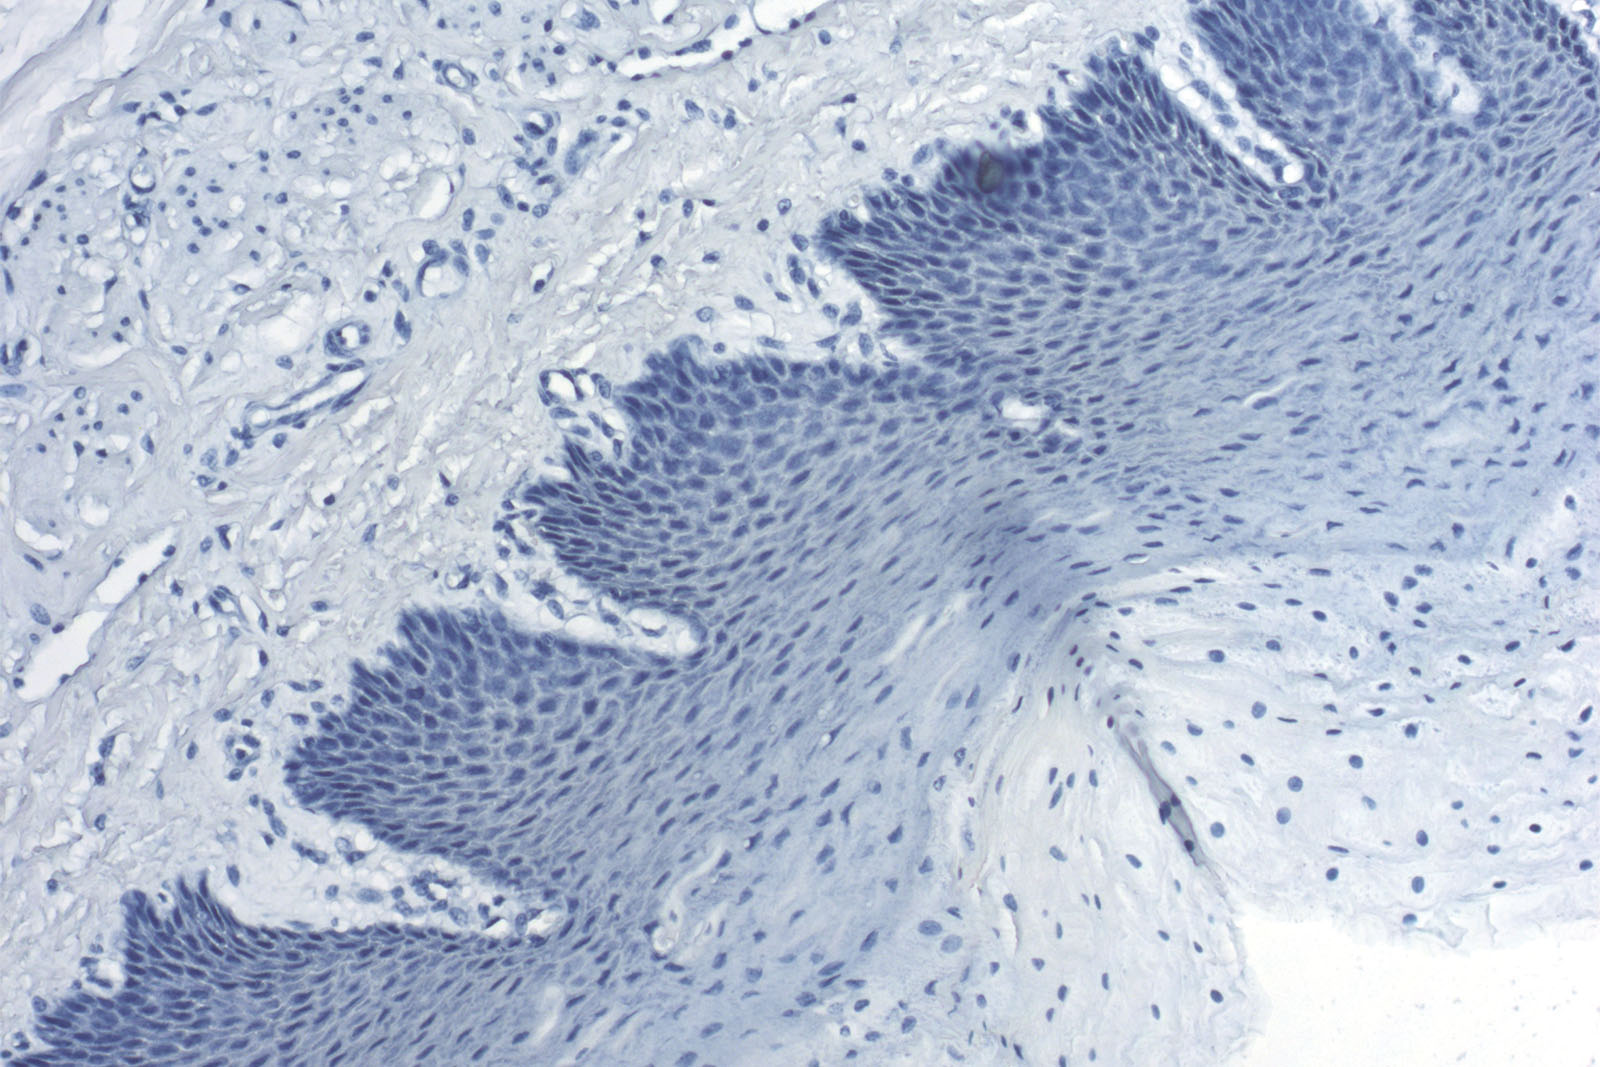

Hematoxylin acc. to Weigert is used in combination with various special (trichrome) stains. Because of its resistance to acidic solutions, it retains the dye and stains nuclear membranes. Unlike the standard hematoxylins used in histology, such as hematoxylins acc. to Harris, Mayer, Mayer-Lillie, and Gill, Hematoxylin acc. to Weigert contains ferric ions that create resistance to acidic solutions and sudden pH value changes. Hematoxylin acc. to Weigert is most commonly used in the following trichrome methods: A.F.O.G., Gomori Trichrome, Masson-Goldner Trichrome, Masson Trichrome, Van Gieson Trichrome, Elastica-Van Gieson and Weigert-Van Gieson. Most of those methods are used for staining muscle and connective fibers.